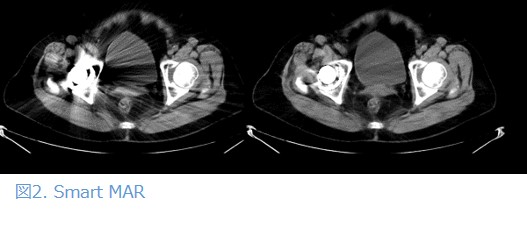

Smart MAR

Revolution Maximaでは、金属アーチファクトの低減を行うSmart MARという機能が搭載されています。当院の80列CTは金属アーチファクト低減機能がないため、金属デバイスの入った患者はできるだけRevolution Maximaで撮影をするようにしています。